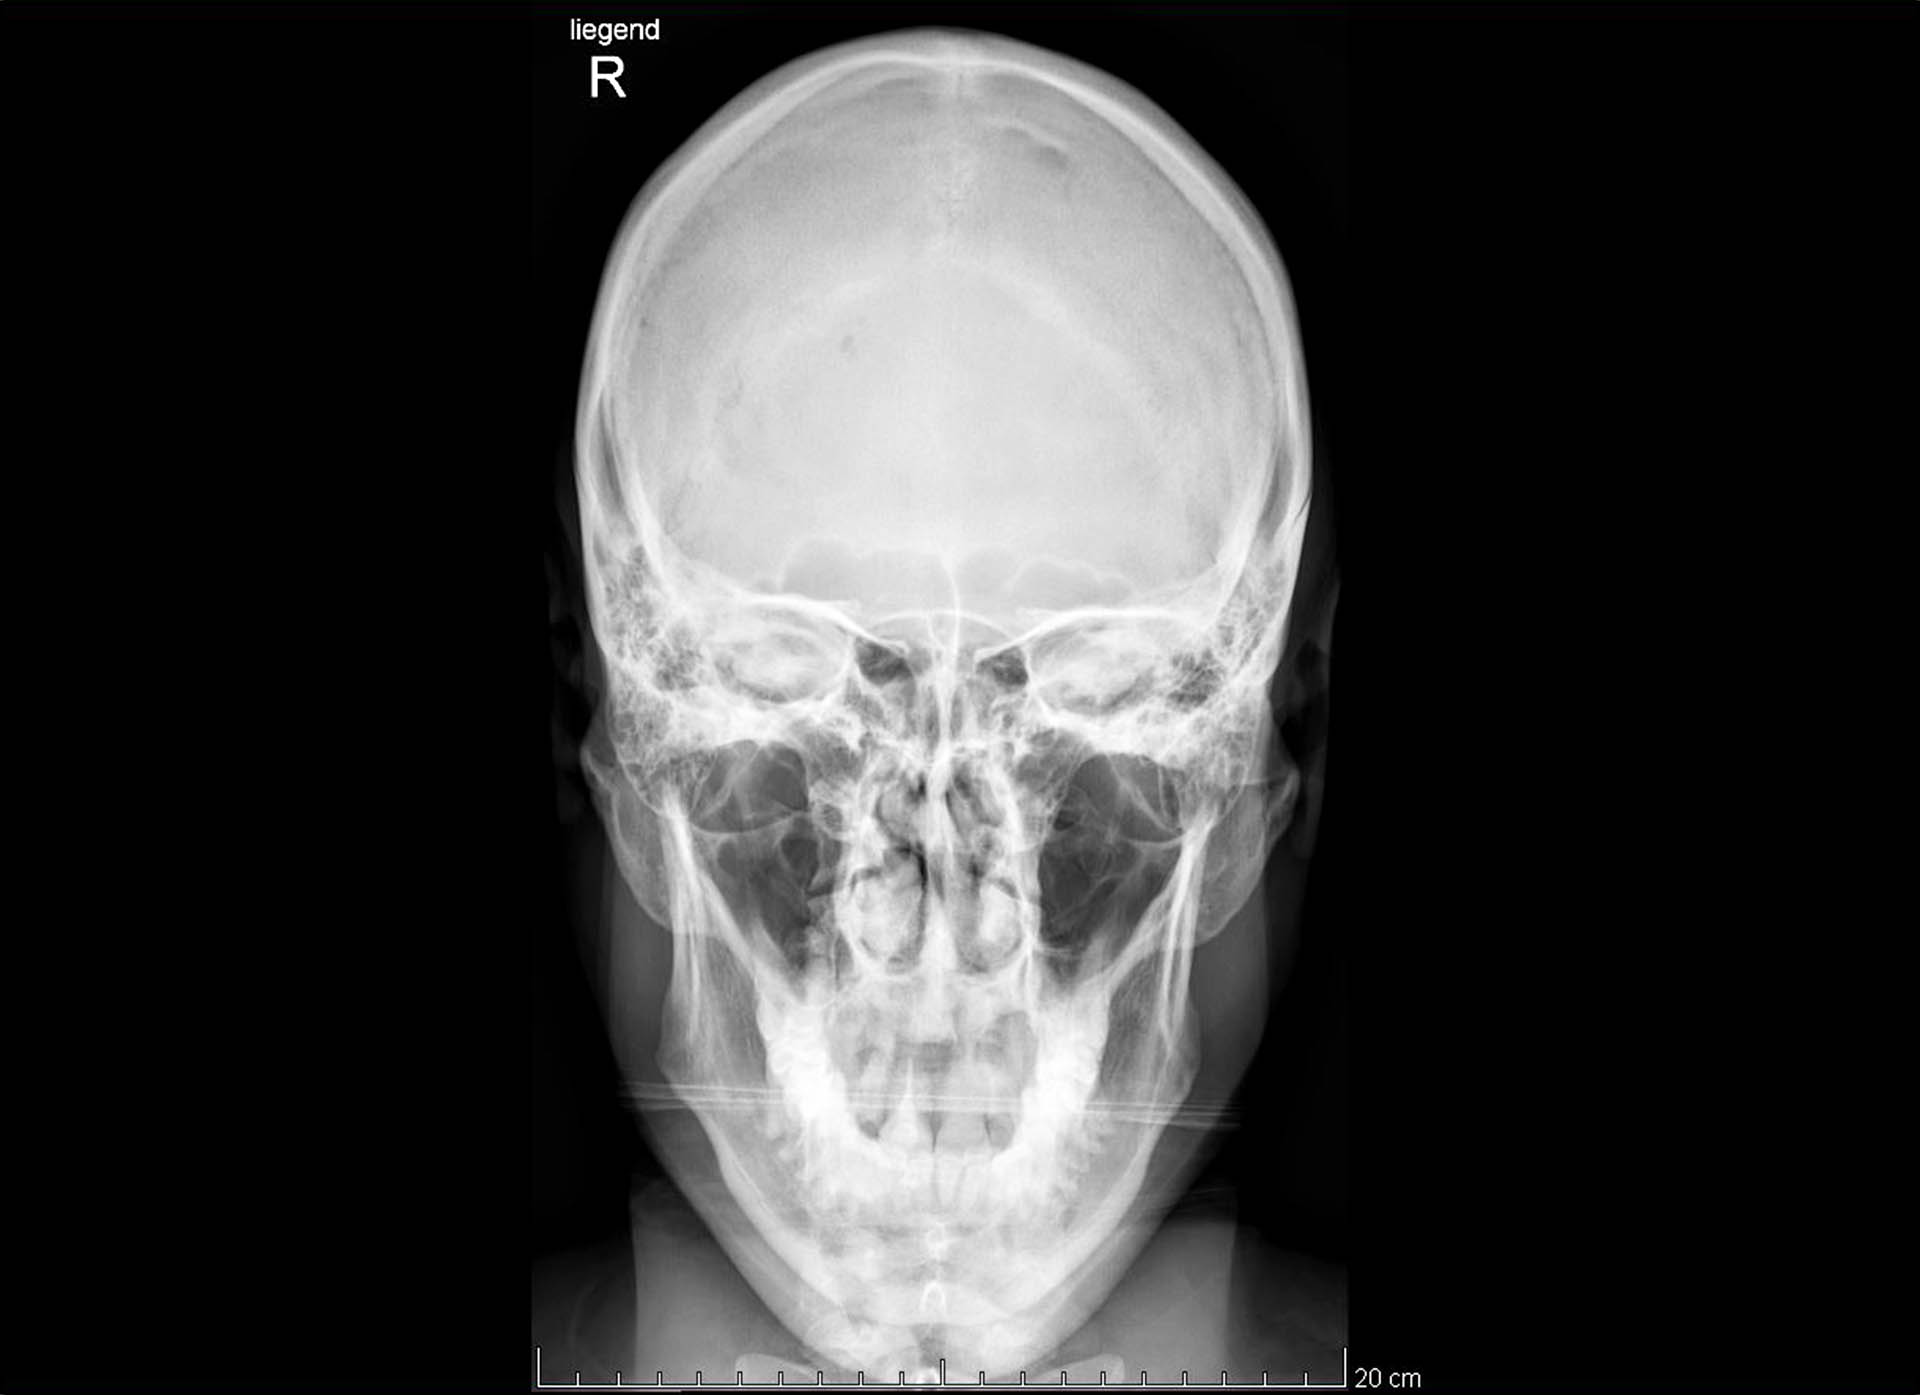

Bilder zu zeigen, wo eine Skitour auch mal im Krankenhaus und nicht zwangsweise bei einem Weißbier auf der Sonnenterrasse enden darf, die Abfahrt auch mal 1300 Hm Bruchharschgewürge bedeuten kann, wo definitiv gar nichts staubt außer die Wundkompressen, die man sich abends auf das verrenkte Knie wickelt, mag zwar nicht Publikumswirksam sein aber es beruhigt mein Gewissen. Meinem Wunsch auch mal ein Lächeln zu zeigen, wo ein Zahn fehlt und ein eingetrockneter Bluttropfen noch an der Nase klebt möchte ich hiermit ebenfalls nachkommen.